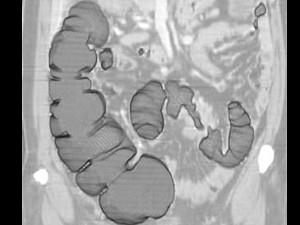

问题 女,56岁,腹胀、腹痛、左下腹包块三月余,无肛门排气,影像检查如图,最可能的诊断是 ( )

选项 A、乙状结肠淋巴瘤 B、乙状结肠息肉 C、乙状结肠结核 D、乙状结肠腺癌 E、乙状结肠crohn病

答案 D